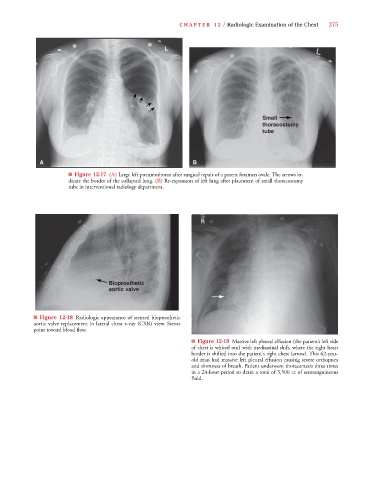

C HAPTER 12 / Radiologic Examination of the Chest 275

Small

thoracostomy

tube

A B

■ Figure 12-17 (A) Large left pneumothorax after surgical repair of a patent foramen ovale. The arrows in-

dicate the border of the collapsed lung. (B) Re-expansion of left lung after placement of small thoracostomy

tube in interventional radiology department.

Bioprosthetic

aortic valve

■ Figure 12-18 Radiologic appearance of stented bioprosthetic

aortic valve replacement in lateral chest x-ray (CXR) view. Stents

point toward blood flow.

■ Figure 12-19 Massive left pleural effusion (the patient’s left side

of chest is whited out) with mediastinal shift, where the right heart

border is shifted into the patient's right chest (arrow). This 62-year-

old man had massive left pleural effusion causing severe orthopnea

and shortness of breath. Patient underwent thoracentesis three times

in a 24-hour period to drain a total of 3,500 cc of serosanguineous

fluid.